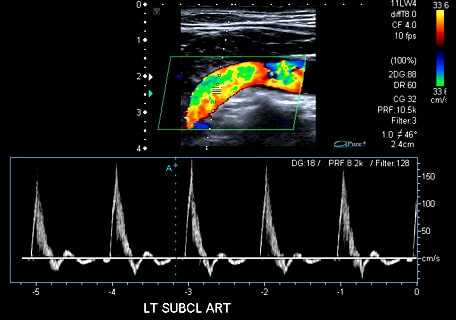

Возможности ультразвуковых приборов позволяют не только оценить размеры, форму и структуру стенки сосуда, но и исследовать характеристики кровотока. Это достигается с помощью доплерографии и цветного допплеровского картирования. Доплерография основана на регистрации ультразвукового сигнала от движущихся эритроцитов и изменении скорости этого сигнала в зависимости от приближения или удаления этих частиц к датчику. Скорость кровотока, определяемого доплерографией, является показателем проходимости сосудов ниже места исследования или в местах сужения сосуда. В суженых местах она значительно усилена; если же существует препятствие для оттока крови ниже места исследования, то скорость снижается.

Пациент укладывается на кушетку на спину справа от доктора. Открывается живот и обе ноги полностью. Ультразвуковой датчик смазывается гелем, для лучшего контакта с кожей пациента. Исследование начинается линейным датчиком с области паха. Оцениваются общие бедренные артерии. Если кровоток по ним магистральный, проводится дальнейшее исследование поверхностных и глубоких бедренных артерий, подколенной и артерий голени, для чего пациента необходимо переворачивать на живот. Для оценки кровотока на стопе изучаются тыльная артерия стопы и задняя тибиальная артерия позади лодыжки. При критической ишемии для улучшения кровенаполнения пациента могут попросить опустить ногу вниз. При исследовании отмечается окрашивание артерий в режиме цветного допплеровского картирования, в обычном B-режиме изучается строение стенки артерии, отмечается наличие атеросклеротических бляшек, патологических расширений (аневризм). Обязательно измеряется скорость кровотока по артериям. Для оценки возможности использования подкожных вен для шунтов определяется их диаметр, ход и проходимость. После исследования артерий на ногах необходимо изучить состояние брюшной аорты и подвздошных артерий. Для этого берется другой (конвексный) датчик и доктор через живот выводит крупные сосуды. Необходимо оценить проходимость, состояние стенки аорты и подвздошных артерий, скорость и характер кровотока по ним.